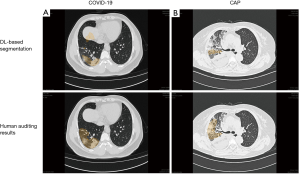

The DL-based segmentation algorithm was built in-house on the InferScholar research platform by InferVision (https://www.infervision.com/, Beijing, China) to segment the infected pneumonia areas and generate quantitative measurements of segmented masks. The algorithm development and validation processes have been described previously in detail (10). Briefly, this algorithm was implemented with a U-net-like deep convolution neural network model and employed to segment regions of interest (ROIs), including lungs, lobes, and detected opacities. These automatic segmented ROIs were subsequently reviewed by 3 experienced radiologists who were blinded to the patients’ clinical status. Radiologists were asked to audit the DL-derived results independently, and adjust the segmented ROIs manually if necessary. This manual adjustment included enlarging or shrinking the ROIs based on the subjective evaluations by radiologists who had reached a consensus, removing obvious false positives, such as vascular artifacts, subpleural interstitial changes, and adding missed lesions (false negatives) by manual annotation with the hand tool implemented in the platform. Eventually, after human auditing, the delineated ROIs were processed into the algorithm analysis module to generate quantitative measurements, including the infected lobe numbers, the percentage of involved lesions’ volumes (of the whole lung and each lobe), and lesion percentages based on different CT attenuation values. Figure 1 depicts our proposed methodological framework for human-centered segmentation auditing derived from DL and radiomic model building.

Quantitative CT measurements generated by DL-based segmentation and human auditing

After a deep examination of false positives and negatives of the AI-enabled segmentation results and the insufficiently segmented regions, final segmentation masks were confirmed by 3 experienced radiologists and human auditing (Figure 2). The quantitative CT measurements were obtained and are set out in Table 2. The results showed that the numbers of infected lobes were significantly lower in the COVID-19 group [median (IQR): 4 (3 to 4)] than the CAP group [4 (4 to 5)] (P=0.031) Concerning the percentage of lung involvement in the whole lung, that of the CAP group was significantly more elevated than that of the COVID-19 group [median (IQR): 1.83% (0.65%, 4.42%) vs. 6.40% (2.77%, 11.11%); P<0.001]. Similarly, the percentage of lung involvement per lobe was significantly higher in the CAP group than the COVID-19 group, except for that of the right upper lobe [1.81 (0.09, 5.28) for the COVID-19 group vs. 1.32 (0.14, 7.02) for the CAP group; P=0.649].